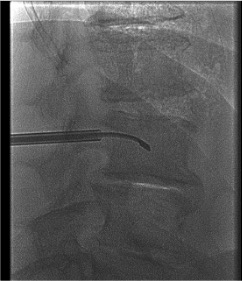

Lateral View โ Depth Control

- Advance trocar to posterior 25% of vertebral body depth on lateral view before inserting curved cannula

- Insert curved cannula through trocar; advance to center of the vertebral body (50% depth) on lateral โ this is the BVF location

- Correct lateral position: tip slightly posterior to true center (posterior 40–50% of body depth)

- Stop immediately if trocar or cannula approaches the anterior 25% on lateral โ risk of anterior cortex breach

- Anterior cortex breach = potential injury to great vessels or viscera โ abort and obtain CT